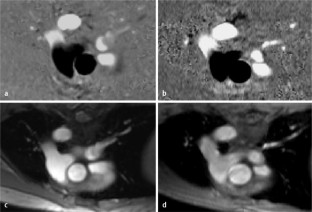

Abb. 1

Abb. 2

Abb. 3

Abb. 4

Abb. 5

Abb. 6

Abb. 7

Abb. 8

Abb. 9

Abb. 10

Abb. 11

Abb. 12

Abb. 13

Abb. 14